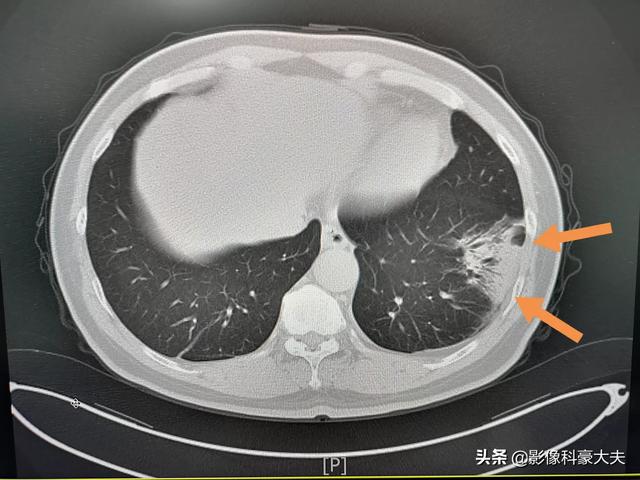

この中年男性は、3日間の咳と発熱があり、CTで左下肺炎が認められ、亜分節に沿って分布し、比較的高密度であった(地硝子影ではない)。肺門側に気管支気腹徴候が認められ、血球数の増加を伴っていたため、コロナウイルスではなく、一般的な肺炎であった。

2.肺炎の画像的特徴を有する:肺に炎症性変化があることを意味し、肺の外側の帯状に明らかな複数の小さな斑状影や間質性変化、さらには両肺に複数の地中影や浸潤影などの変化を示します。ウイルスが肺に侵入した後、肺にうっ血や水腫が生じ、X線やCTで高密度の影が観察されるからです。

②胸部CTを撮影すると、初期には多発性の斑状陰影や間質性変化を示唆することがあり、肺外帯に明らかで、その後の検討で両肺に多発性の地中影や浸潤影が生じ、重症例では固形肺病変が出現する。

②.肺炎の画像的特徴が胸部に認められる。

初期には複数の小さな斑状影と間質性変化を呈し、両肺に多発する地硝子影や浸潤影へと進行し、重症例では肺に固形変化が生じ、一般に「白い肺」と呼ばれる状態になることもある。

2.肺のCTで、地硝子影または浸潤影(CTフィルム上の肺の白い影)を認める。